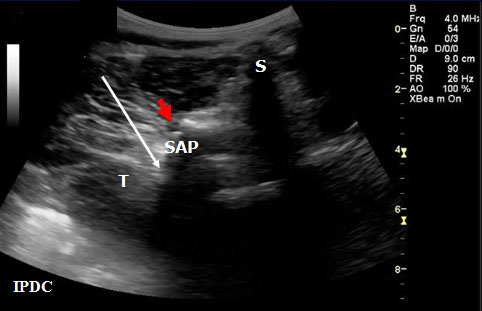

In order to visualize the appropriate structures for lumbar medial branch blocks, a low frequency curved array transducer (2-6 MHZ) is needed.[34] The views utilized to define the sonoanatomy are the cross axis and the long axis views (Figure 11). In the long axis view, the appropriate level of the spine can be identified (Figure 12). The cross axis view demonstrates the step-off deformities between the spinous, superior articular, and transverse processes (Figure 13). In some cases the facet joint between the superior and inferior articular processes can be visualized in the cross axis view. The anatomical landmarks for the L5 dorsal ramus can be difficult to visualize with ultrasound secondary to bony artifact from the iliac crest.

Figure 13. Sonographic cross axis view demonstrating the spinous, transverse and superior articular processes. The white arrow demonstrates the needle pathway for blockade of the lumbar medial branch. Red arrow = Zygapophysial Joint. S = Spinous Process. SA = Superior Articular Process. T = Transverse Process.

Greher et al.[34] developed an ultrasound methodology for the lumbar medial branch block. First, the patient is placed in the prone position with a pillow under their abdomen to reduce the lumbar lordosis. The appropriate level of the lumbar spine is identified under the long axis view, and the level to be anesthetized is centered. The transducer is then rotated 90° to the cross axis view. The step-off deformity is seen between the superior articular process and the transverse process. Under real-time ultrasound guidance with an in plane technique, a 22-gauge spinal needle is inserted from lateral to medial (Figure 13). The insertion angle is approximately 45° to 60° to the skin. The needle is directed down to the junction between the superior articular process and the superior border of the transverse process. Once bony contact is reached the transducer is rotated back to the long axis view to confirm that the needle tip is at the cranial edge of the transverse process. Local anesthetic is then injected to anesthetize the targeted medial branch.